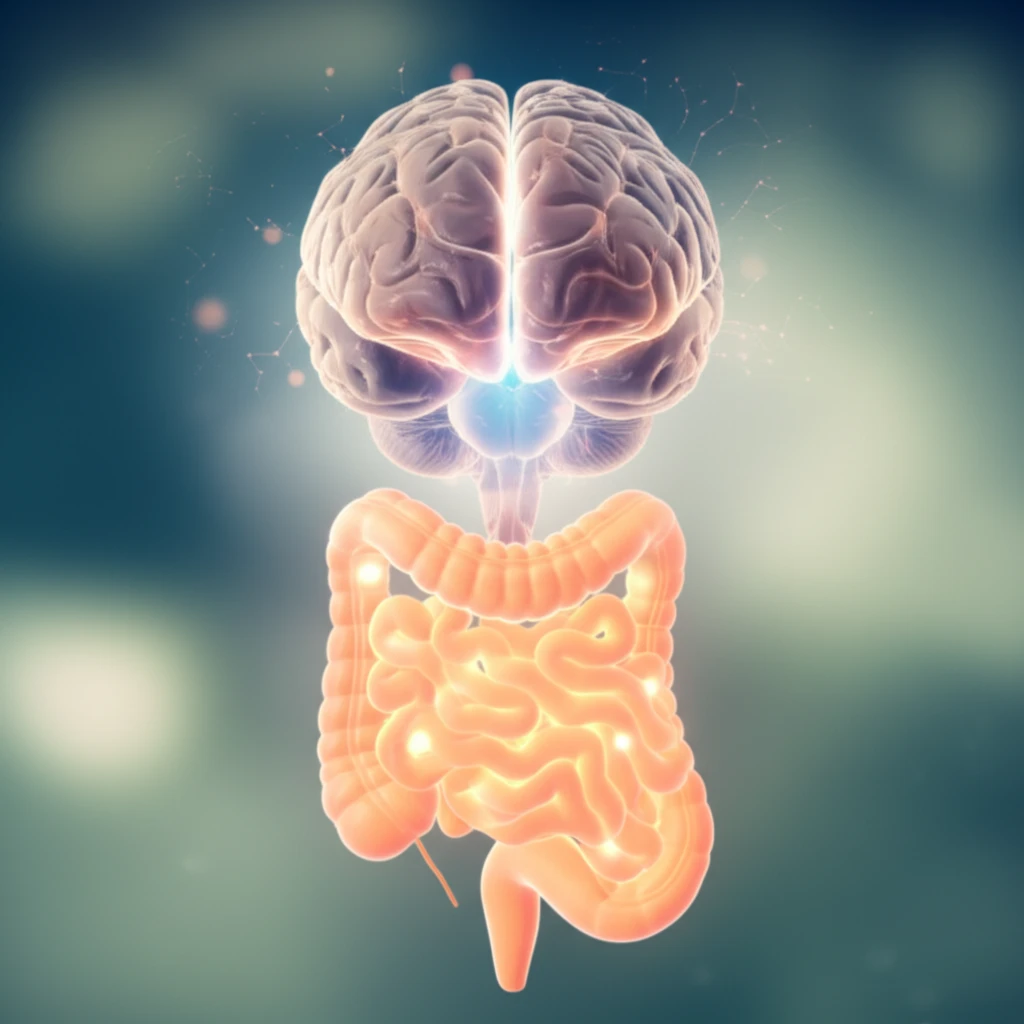

Irritable Bowel Syndrome (IBS) is a widespread gastrointestinal disorder characterized by persistent abdominal pain, bloating, and altered bowel habits. Millions worldwide grapple with the debilitating effects of IBS, often leading to a significant reduction in their quality of life. The quest for effective treatments has been ongoing, with a focus on understanding the intricate relationship between the gut and the brain.

Within this complex interplay, the role of serotonin, a neurotransmitter crucial for both mood regulation and gut function, has gained significant attention. Serotonin receptors, particularly the 5-HT1a receptors, are emerging as key players in modulating pain signals within the gut-brain axis. These receptors are strategically located throughout the body, including the ventrolateral medulla (VLM) in the brain, which plays a critical role in pain processing.

The core of IBS pain often lies in the brain's misinterpretation of signals from the gut. The VLM, a region within the brainstem, acts as a central processing unit for pain signals. When the gut experiences distress, such as the contractions or inflammation, these signals are relayed to the VLM, which then processes and amplifies the pain sensation. The 5-HT1a receptors, abundant in the VLM, provide a potential target for medications aiming to modulate these pain signals.